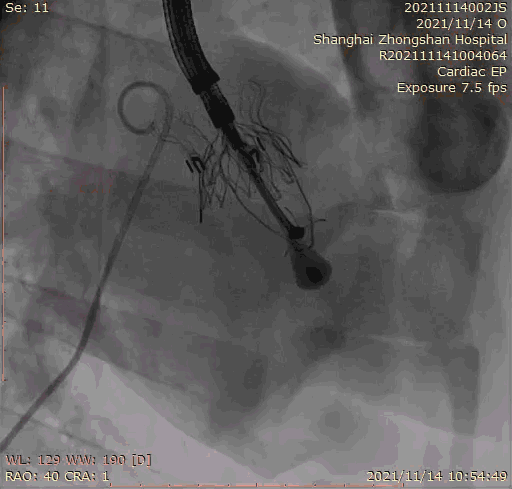

本次臨床前研究經右側頸靜脈置入LuX-Valve Plus輸送系統可調彎鞘管,在DSA及超聲引導下將人工三尖瓣瓣膜植入到原有三尖瓣位置,利用獨特的錨定技術將人工瓣膜支架可靠固定在預定的位置。

Lux-Valve是全球第一款具有我國完全自主知識產權的經導管介入三尖瓣置換系統,利用前瓣夾持及室間隔錨定的復合方式進行瓣膜裝置的固定,不依賴瓣環徑向支撐力,同時采用自適應復合裙邊材料,有效的貼合密封柔軟的三尖瓣瓣環,針對于三尖瓣返流的患者有優異的療效。Lux-Valve Plus采用全新的經血管輸送系統,經頸靜脈入路創傷更小,可以進一步降低手術風險。相信在后期正式臨床研究開展中,Lux-Valve Plus必定會為更多的三尖瓣反流患者帶來福音。